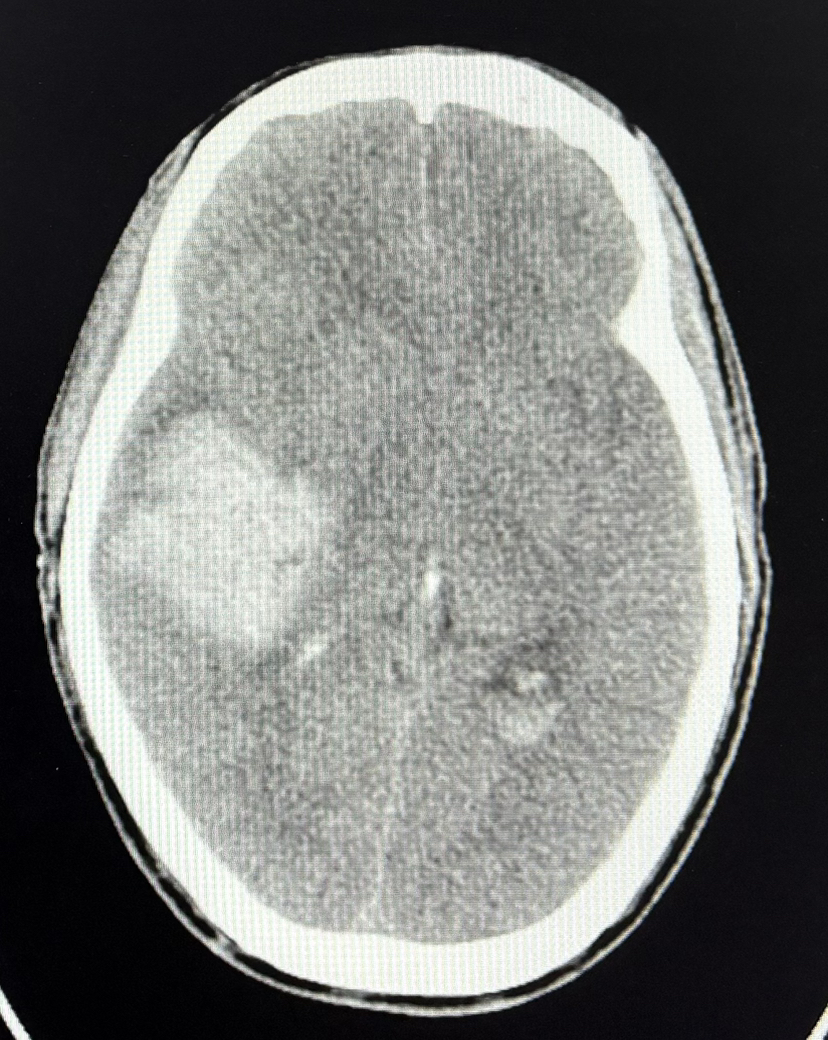

CT示:脑出血